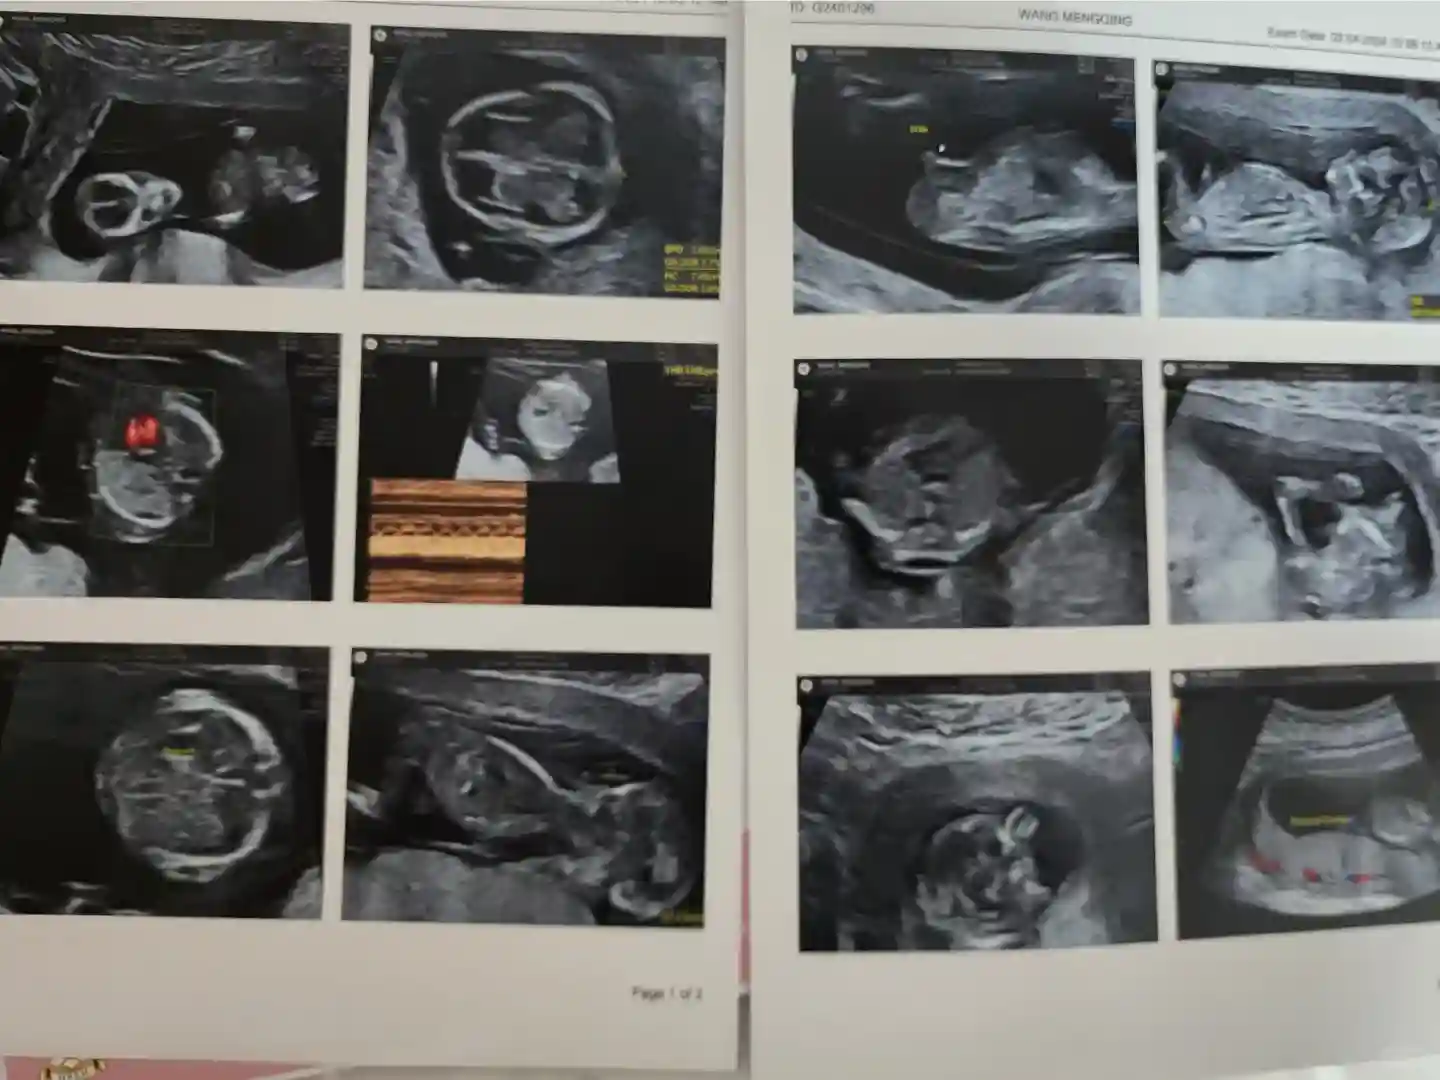

8 由护士带到医生的诊室 了解信息 之后医生会给做一个b超 跟内地的大排畸差不多 还知道了男女 并且 加了医生私人微信 有问题可以随时问诊 这次来做无创plus所以开了抽血单